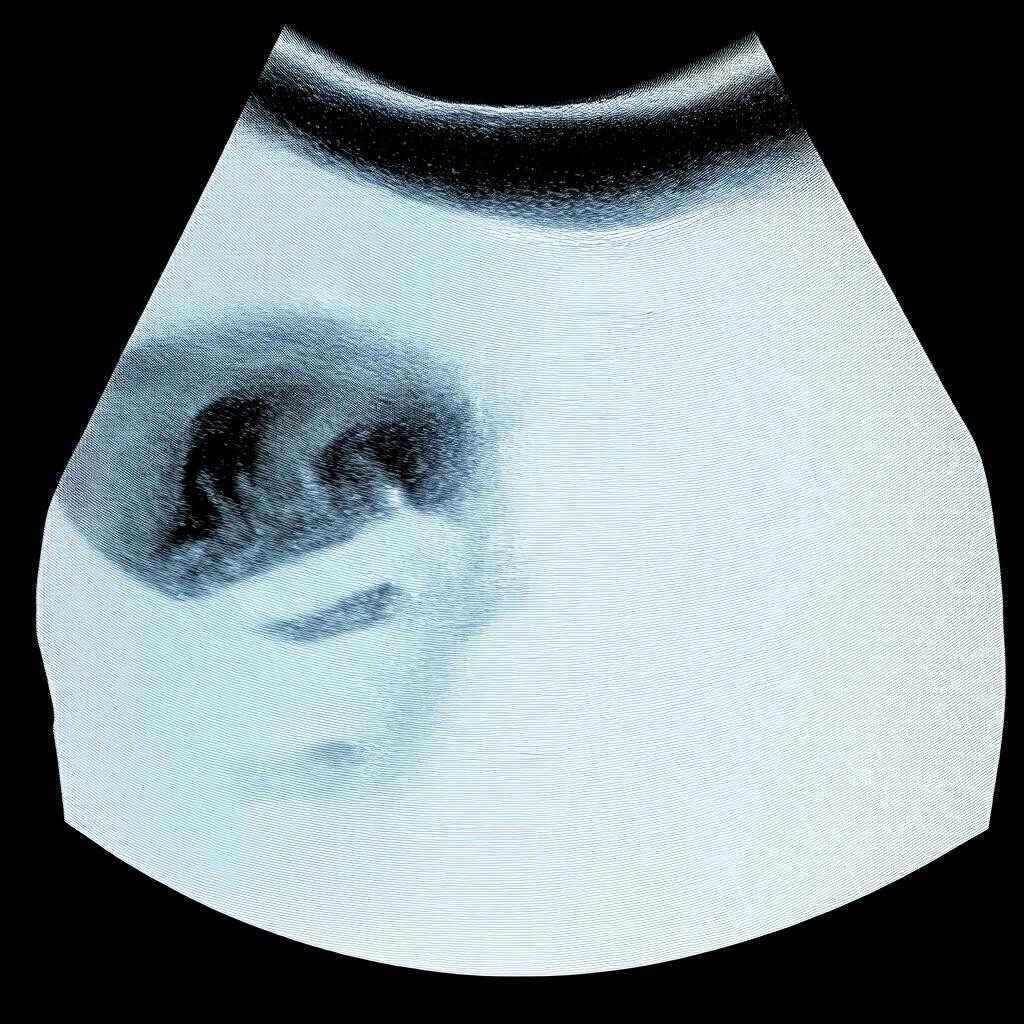

Третье плановое УЗИ является важным этапом наблюдения за беременностью. Оно проводится в третьем триместре и позволяет оценить состояние плода, плаценты и готовность организма матери к родам. Врачи рекомендуют проходить это обследование в определённые сроки, чтобы получить максимально точные данные.

Третье плановое УЗИ обычно проводят на 30-34 неделе беременности. Этот период выбран не случайно:

• Плод уже достаточно развит для оценки всех органов и систем.

• Можно определить предлежание плода (головное, тазовое и др.).

• Оценивается состояние плаценты и количество околоплодных вод.

Во время третьего УЗИ врачи обращают внимание на несколько ключевых параметров:

1. Размеры и вес плода: Оценивается соответствие сроку беременности.

2. Положение плода: Определяется предлежание, которое важно для планирования родов.

3. Состояние плаценты: Проверяется её зрелость и расположение.

4. Количество околоплодных вод: Исключается многоводие или маловодие.

5. Работа сердца и кровоток: Проводится допплерометрия для оценки кровоснабжения плода.